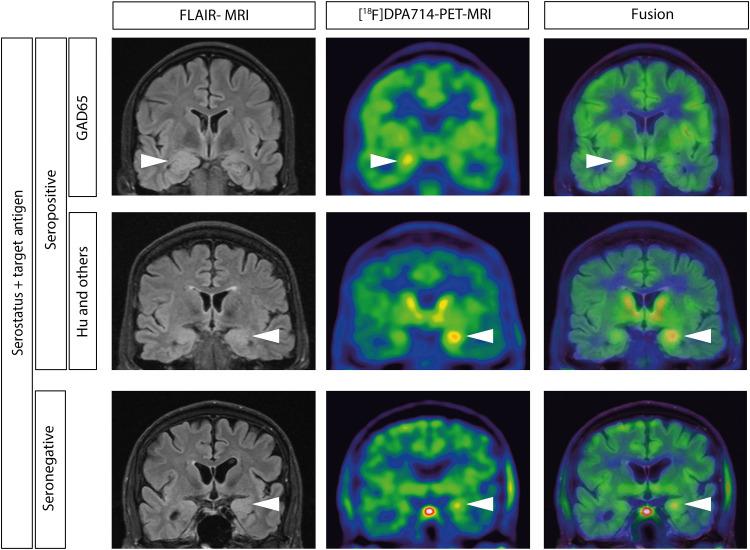

Autoimmune limbic encephalitis (ALE) presents with new-onset mesial temporal lobe seizures, progressive memory disturbance, and other behavioral and cognitive changes. CD8 T cells are considered to play a key role in those cases where autoantibodies (ABs) target intracellular antigens or no ABs were found. Assessment of such patients presents a clinical challenge, and novel noninvasive imaging biomarkers are urgently needed. Here, we demonstrate that visualization of the translocator protein (TSPO) with [F]DPA-714-PET-MRI reveals pronounced microglia activation and reactive gliosis in the hippocampus and amygdala of patients suspected with CD8 T cell ALE, which correlates with FLAIR-MRI and EEG alterations. Back-translation into a preclinical mouse model of neuronal antigen-specific CD8 T cell-mediated ALE allowed us to corroborate our preliminary clinical findings. These translational data underline the potential of [F]DPA-714-PET-MRI as a clinical molecular imaging method for the direct assessment of innate immunity in CD8 T cell-mediated ALE.

自身免疫性边缘性脑炎(ALE)表现为新发性内侧颞叶癫痫、进行性记忆障碍以及其他行为和认知改变。CD8 T 细胞被认为在自身抗体(ABs)针对细胞内抗原或未发现 ABs 的情况下发挥关键作用。评估这些患者具有临床挑战性,迫切需要新的非侵入性成像生物标志物。在这里,我们证明使用 [F]DPA-714-PET-MRI 可视化转位蛋白(TSPO)可在疑似 CD8 T 细胞 ALE 患者的海马体和杏仁核中显示出明显的小胶质细胞激活和反应性神经胶质增生,与 FLAIR-MRI 和 EEG 改变相关。将这些转化数据反向翻译到神经元抗原特异性 CD8 T 细胞介导的 ALE 的临床前小鼠模型中,使我们能够证实我们的初步临床发现。这些转化数据强调了 [F]DPA-714-PET-MRI 作为一种临床分子成像方法,可直接评估 CD8 T 细胞介导的 ALE 中的固有免疫。